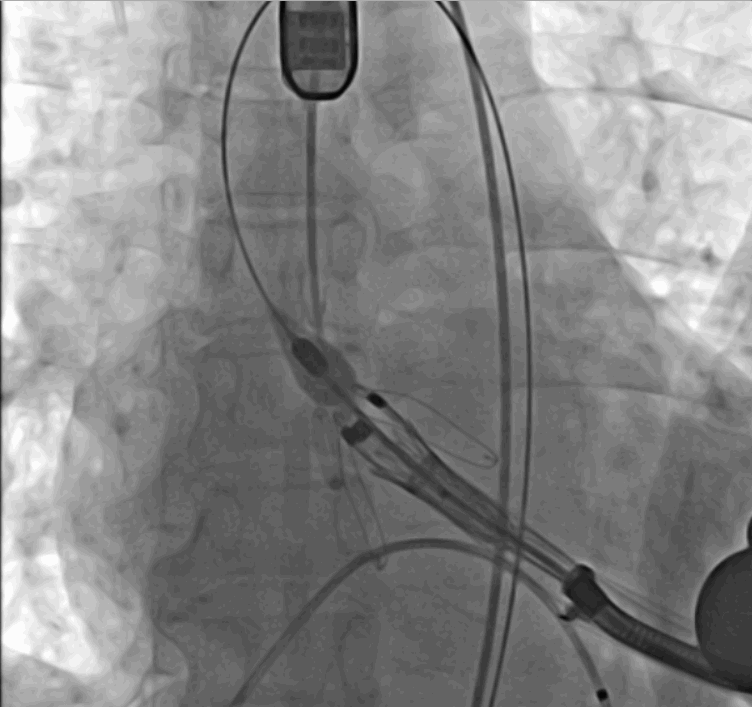

术中瓣膜释放过程